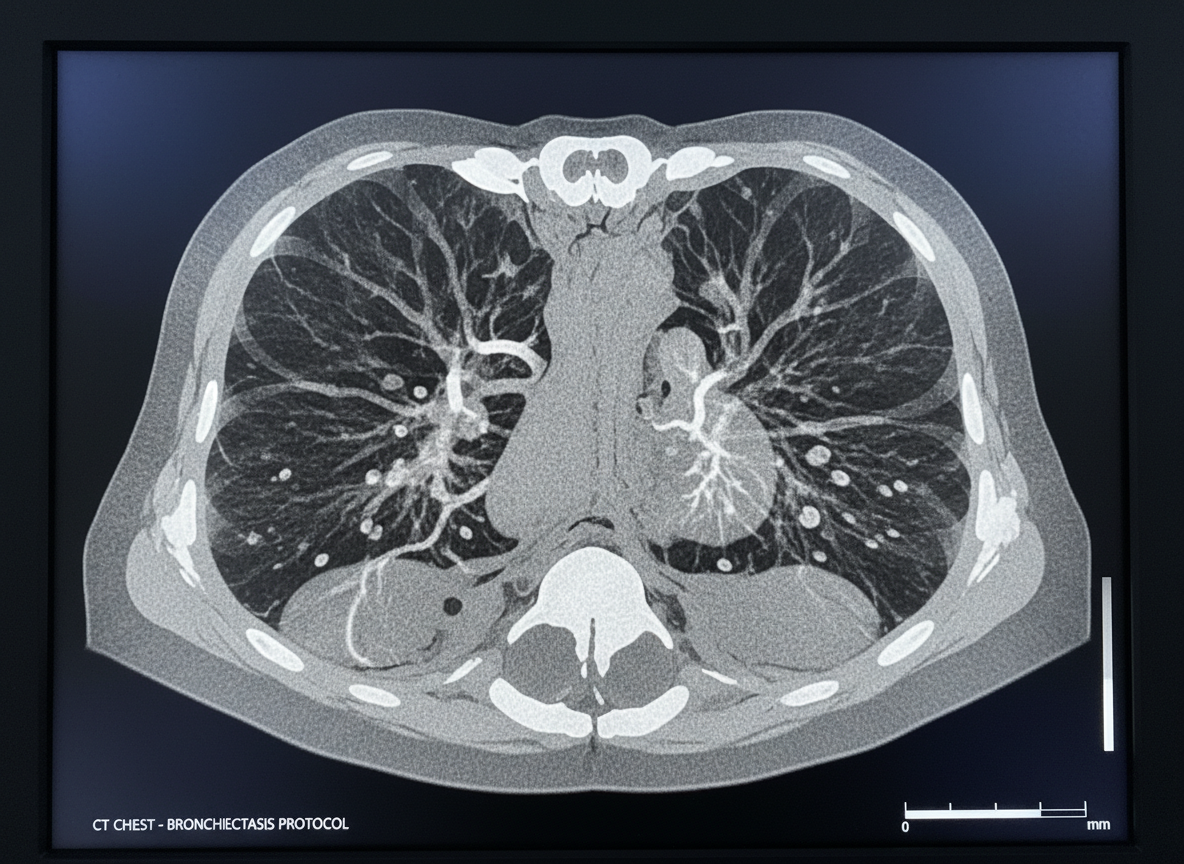

기관지확장증이 바로 그렇습니다. 과거에 앓았던 결핵이나 폐렴의 흔적으로 기관지가 영구적으로 늘어나고 벽이 약해진 상태입니다. 이 경우 피로하거나 감기에만 걸려도 혈관이 터지며 피가래가 나올 수 있습니다. 많은 분들이 "저는 담배도 안 피우는데요?"라고 반문하지만, 어릴 적 앓았던 홍역이나 백일해가 원인이 되어 성인이 된 후 증상이 나타나기도 합니다. 만약 아침마다 누런 가래가 끓고 종종 피가 비친다면, 폐 CT를 통해 내 기관지 상태를 점검해 보는 것이 현명합니다.

A: 가장 기본적으로는 흉부 X-ray를 촬영하지만, 미세한 기관지확장증이나 초기 병변은 X-ray에 안 보일 수 있습니다. 따라서 객혈 증상이 있다면 저선량 흉부 CT 촬영을 권장합니다.